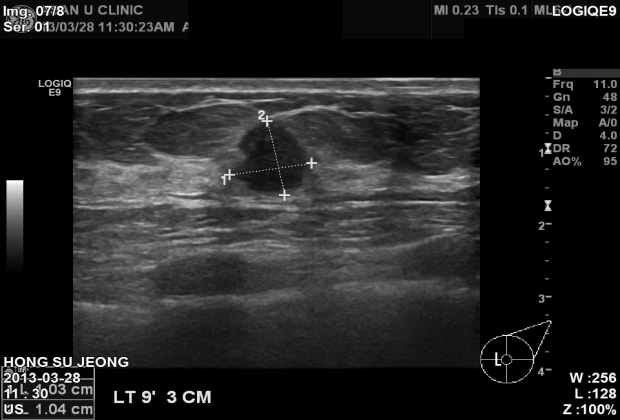

맛사지 받다가 이상하다는 얘기듣고 검사하러 오셨다가

유방암(2cm미만)으로 본원에서 조직검사 진단되셨으며

서울아산병원에서 치료예정이십니다.